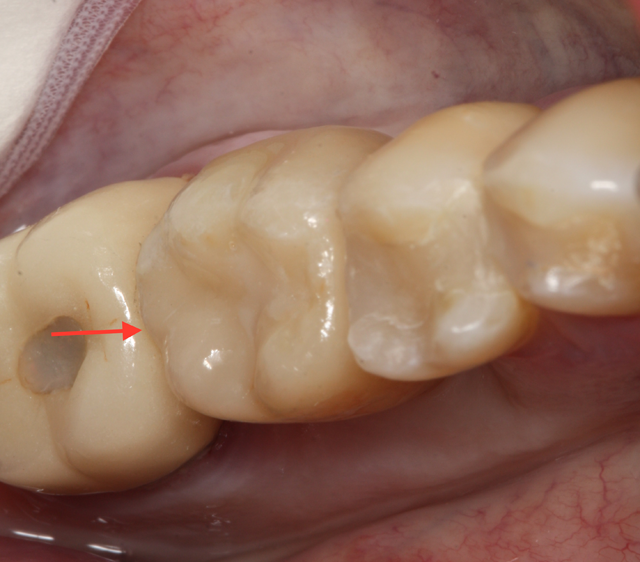

The patient, a healthy 38-year-old male with an unremarkable medical history, presented with a non-restorable tooth #19.

The tooth had a vertical root fracture and recurrent decay. The patient was given an option for an implant at site #19 or a fixed bridge from teeth #18-20. The patient elected to have the tooth extracted and an implant placed immediately at the time of extraction. The implant placement was planned using a CBCT scan and Galaxis software.